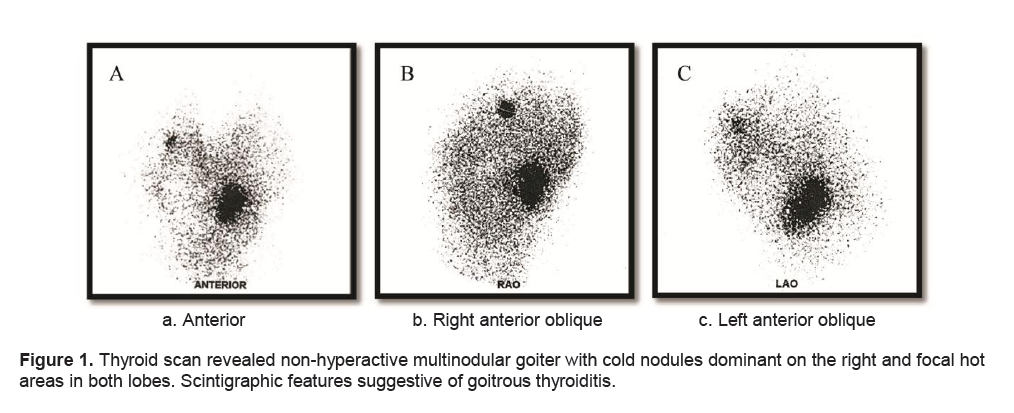

A frail, 71-year-old female in mild respiratory distress presented at the Emergency Room. Her condition started 2 weeks prior to consult she started to experience shortness of breath and easy fatigability. Pertinent in the history was a goiter which was untreated for several years. There was no noticeable rapid enlargement of the thyroid gland, but there was hoarseness for the past 15 years. She noted weight loss in the last 8 months. She had no prior history of neck radiation, nor family history of goiter. Palpitations and easy fatigability were also present. At the time dyspnea became progressive, patient became weak, and appetite started to decrease. Physical examination showed she was tachycardic, tachypneic, febrile with wheezing and crackles on both lung fields. No palpable thyroid nodules and no cervical lympadenopathy were appreciated. Initial impression was pneumonia with marked leukocytosis at 22.70mg/dl with toxic granules. Chest x-ray showed pulmonary nodules and right superior mediastinal mass, inflammatory versus neoplastic in origin. Thyroid function test results showed suppressed TSH 0.01uIU/mL (normal 0.35-4.94uIU/mL), FT3 6.37pg/mL (normal 1.45-3.48), and elevated FT4 2.36 ng/dL (normal 0.71-1.85). Patient underwent thyroid scan which showed non-hyperactive multinodular goiter with cold nodules dominant on the right and focal hot areas in both lobes suggestive of goitrous thyroiditis (Figures 1A, 1B, 1C). Thyrotropin receptor antibodies were negative. Ultrasound of the thyroid revealed bilateral thyroid nodules. The right lobe showed three solid nodules with the following measurements: 2.1 x 1.8 x 1.10 cm (with peripheral vascularity), 3.7 x 3.3 x 2.0 cm, and 5.0 x 3.7cm (with calcifications and minimal internal and peripheral vascularity). Left lower thyroid lobe had complex nodules with the following measurements: 2.0 x 2.4 x 1.8 cm (predominantly solid) and 4.2 x 3.3 x 2.4 cm (with peripheral vascularity). Treatment for her thyrotoxicosis was started with propylthiouracil 50mg/tab 4 tabs every 8 hours. With persistent shortness of breath, a chest CT scan with intravenous contrast was done and it showed several mildly enhancing, well circumscribed pulmonary nodules in both lung fields. The largest nodule measured 1.5cm in its widest diameter, while most of the nodules were subcentimeter in diameter. The enlarged right thyroid lobe spanned an approximate length of 9cm and extended into the superior mediastinum. (Figure 2A). The mass compresses the mid segment of the trachea to the left, narrowing its lumen (Figure 2B). After several days of treatment with antibiotics and anti-thyroid medications, the patient had improved and dyspnea had markedly lessened.

Figure 1. Thyroid scan revealed non-hyperactive multinodular goiter with cold nodules dominant on the right and focal hot areas in both lobes. Scintigraphic features suggestive of goitrous thyroiditis.